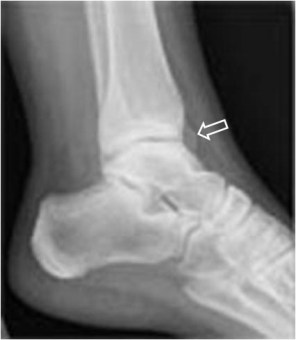

SIGNO DE LA C

Signo de coalición subtalar (fusión calcáneo-astragalina) en la radiografía lateral del tobillo. La «C» se forma por el límite medial de la cúpula talar y el límite posteroinferior del sustentaculum tali.

En la radiografía lateral de tobillo hemos marcado con flechas la «C» que da nombre al signo.

La fusión calcáneo-astragalina (flecha) se comprueba en el corte coronal de TC de tobillo.

Referencia: Lateur LM y cols. Subtalar coalition: diagnosis with the C sign on lateral radiographs of the ankle. Radiology 1994; 193: 847-851.